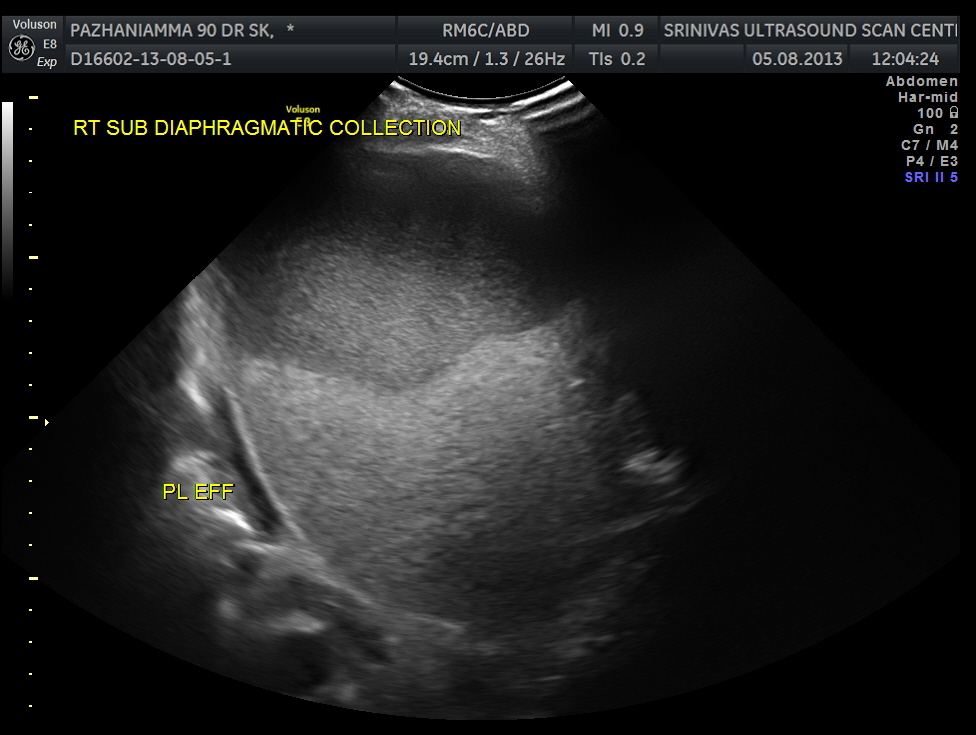

SUB DIAPHRAGMATIC COLLECTION , PROBABLY LOCULATED WAS ALSO SEEN. MINIMAL RIGHT PLEURAL EFFUSION WAS ALSO SEEN.

The diagnosis was : acute calculous cholecystitis , cystic duct stones causing a rupture and fluid collection around the GB and loculated sub diaphragmatic collection with reactive mild right pleural effusion . Endometrial fluid collection needed further evaluation.